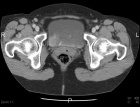

60 year old female presents for further evaluation after a mass was noted during workup related to treatment of a scalp melanoma in situ.